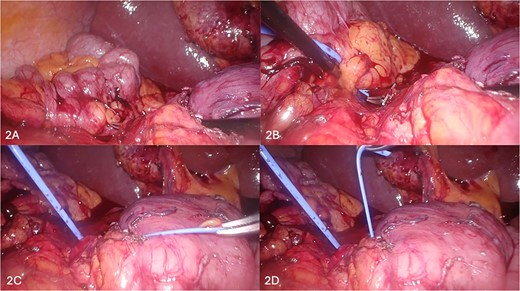

(A–D) Sequential depiction of the plane between annular pancreas and duodenum being defined using Maryland grasper (A, B) and silicone vessiloop (B–D).